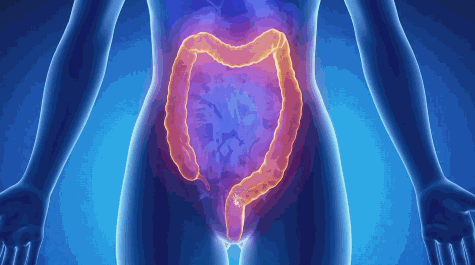

临盆前,准妈妈的身体会发生一些奇妙的变化,肠道中的菌群会转移到产道当中。

那些来自母亲体内的菌群并非我们的敌人,它们迅速占领这颗新生星球的大块领地,也让那些有害的病菌无处落脚。

当然这仅仅是它们带来的其中一个改变,更为重要的是对免疫系统的调节。

过度活跃的免疫系统带来了很多顽固的疾病,如关节炎、哮喘、花粉过敏、动物毛发过敏等等。

初生婴儿与大量益生菌接触能调节他们免疫系统的敏感程度,这一点通常难以被我们注意到。

总的来说这些寄生在人体上的微生物不但能够攘外也能安内。

我们身体上的微生物大概会在两岁半左右开始趋于稳定。